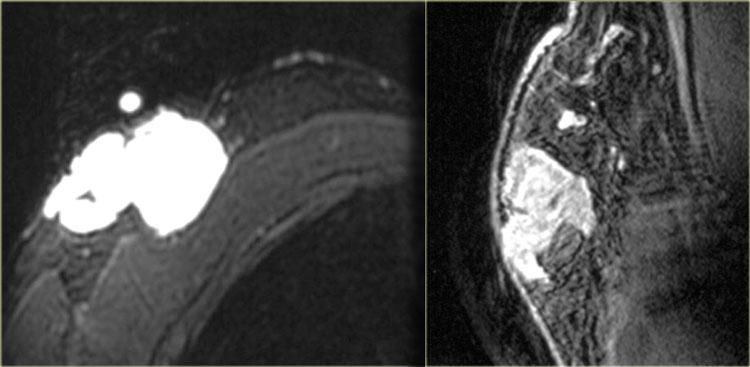

Bên trái là hai trường hợp.

Hình ảnh ngoài cùng bên trái là ung thư ống tuyến xâm lấn biểu hiện dưới dạng khối lớn ngấm thuốc không đồng nhất.

Kế bên là ví dụ về ung thư ống tuyến xâm lấn biểu hiện dưới dạng khối nhỏ hơn với ngấm thuốc dạng viền.

Hình ảnh ngoài cùng bên trái cho thấy một khối bất thường có lan rộng theo ống tuyến, và

bên phải là một khối bất thường lan đến thành ngực nhưng không xâm lấn vào thành ngực.

Không có ngấm thuốc ở thành ngực.